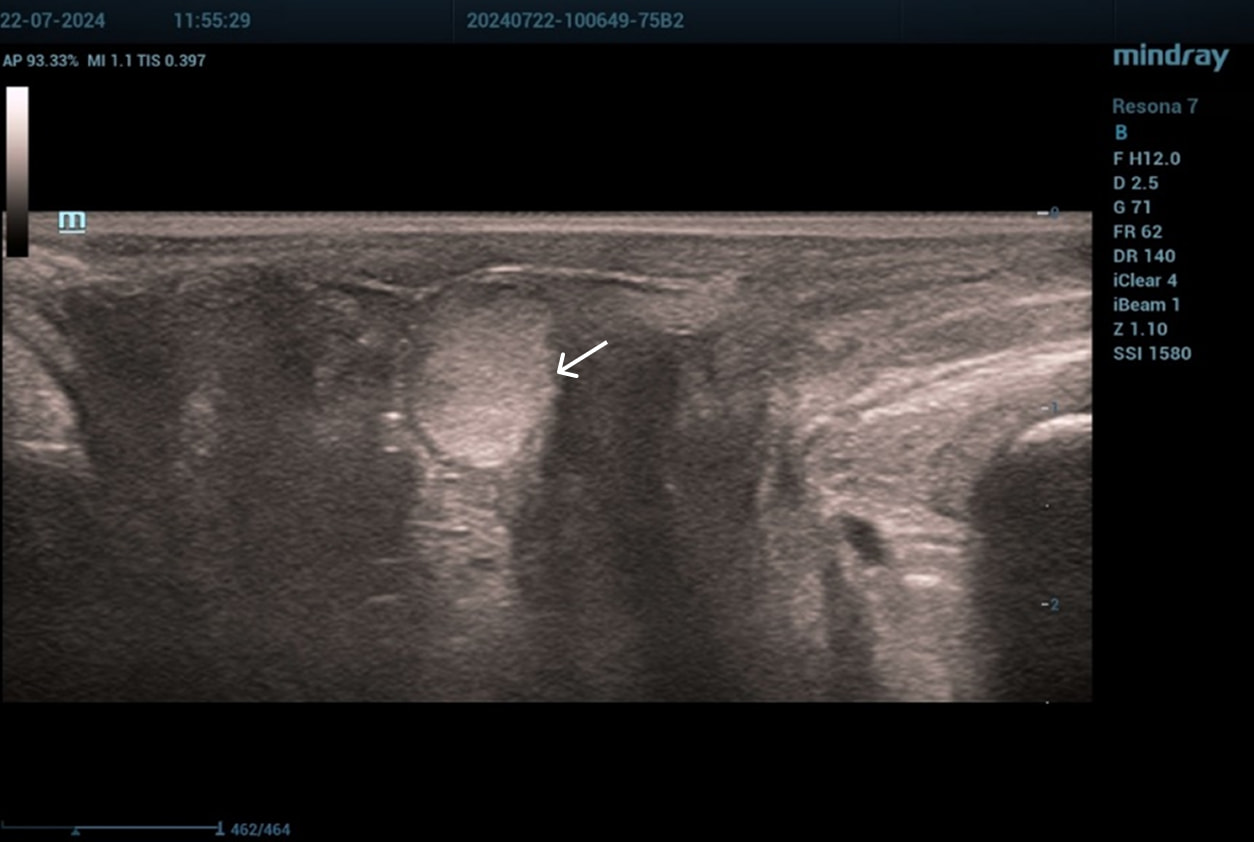

Эхограммы периуретральной области

Трансперинеальный доступ, линейный датчик.

Слева от уретры округлое образование с четкой капсулой и мелкодисперсной взвесью размерами 1,5×1,0 см (филлер с воспалением), справа — анэхогенное овоидное образование (филлер).

Эхограмма 1

Эхограмма 2